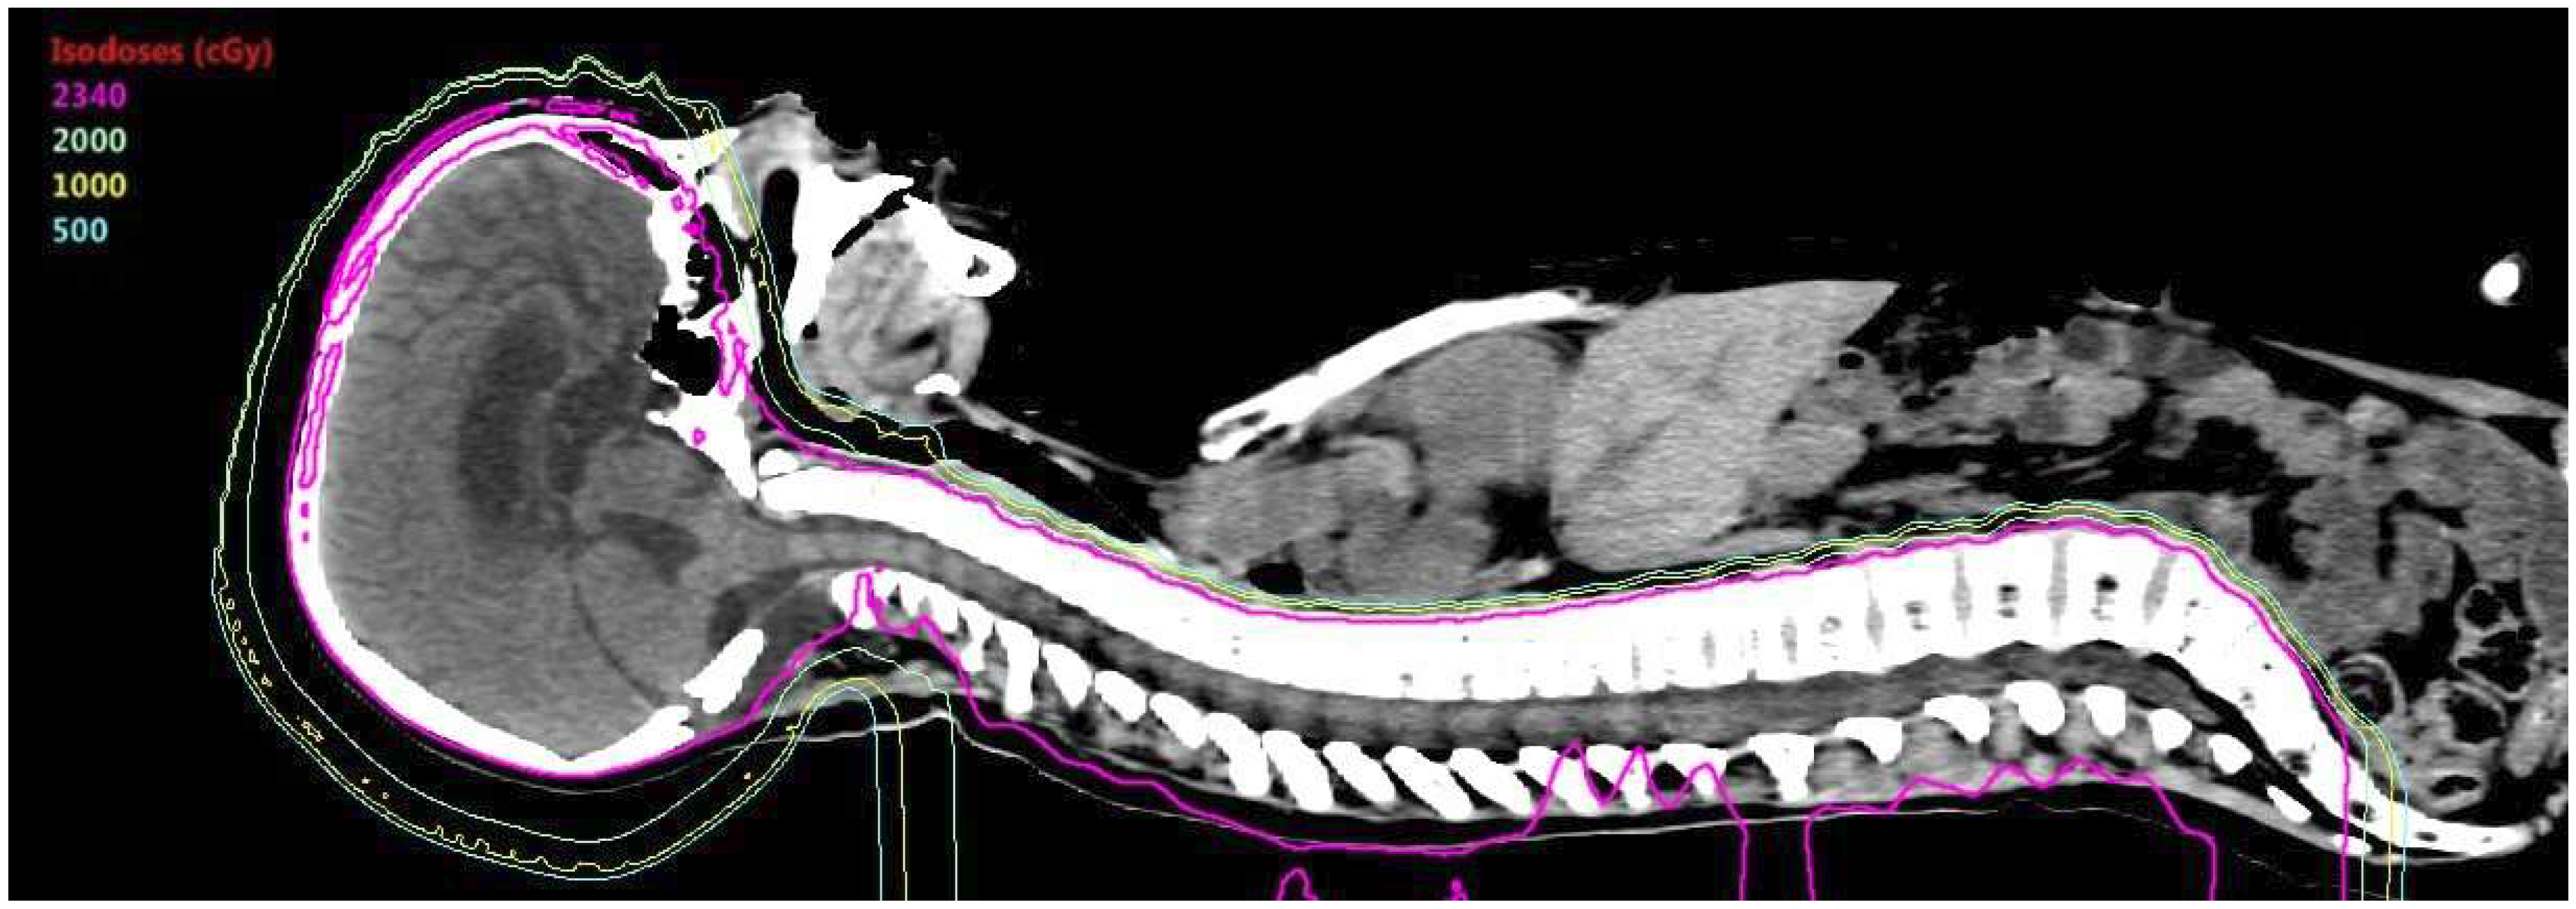

- Brower, J.V.; Gans, S.; Hartsell, W.F.; Goldman, S.; Fangusaro, J.R.; Patel, N.; Lulla, R.R.; Smiley, N.P.; Chang, J.H.; Gondi, V. Proton therapy and helical tomotherapy result in reduced dose deposition to the pancreas in the setting of cranio-spinal irradiation for medulloblastoma: Implications for reduced risk of diabetes mellitus in long-term survivors. Acta Oncol. 2015, 54, 563–566. [Google Scholar] [CrossRef] [PubMed]

- Eaton, B.R.; Esiashvili, N.; Kim, S.; Patterson, B.; Weyman, E.A.; Thornton, L.T.; Mazewski, C.; MacDonald, T.J.; Ebb, D.; MacDonald, S.M.; et al. Endocrine outcomes with proton and photon radiotherapy for standard risk medulloblastoma. Neuro-Oncology 2016, 18, 881–887. [Google Scholar] [CrossRef] [PubMed]

- Wolden, S.L. Protons for craniospinal radiation: Are clinical data important? Int. J. Radiat. Oncol. Biol. Phys. 2013, 87, 231–232. [Google Scholar] [CrossRef] [PubMed]

- Johnstone, P.A.; McMullen, K.P.; Buchsbaum, J.C.; Douglas, J.G.; Helft, P. Pediatric CSI: Are protons the only ethical approach? Int. J. Radiat. Oncol. Biol. Phys. 2013, 87, 228–230. [Google Scholar] [CrossRef] [PubMed]